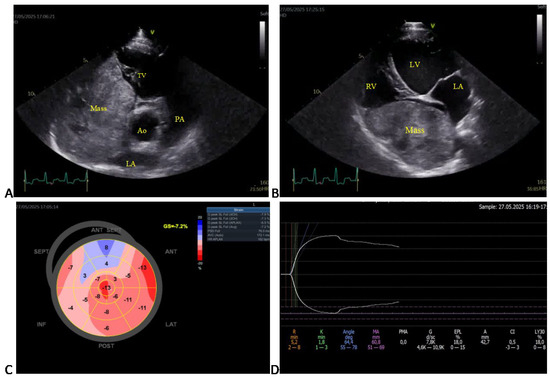

2.6. Echocardiographic Assessment

3.3. Echocardiographic Findings

3.4. Diagnostic Imaging and Cytological Findings